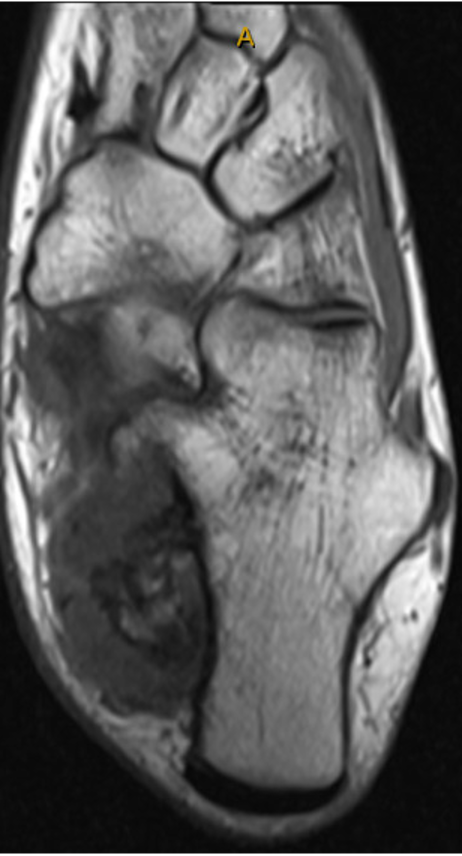

This is a 20-year-old female who presented with a history of a multiply recurrent osteochondroma of her left calcaneus removed in the past by Podiatry. The first excision was when she was 12 years old, and the lesion was thought to be an accessory calcaneus. She was found to have a recurrence at the age of 17, and the lesion was again removed by podiatry. Pathology from this case was consistent with an osteochondroma. It was then, at age 18, that the patient presented to orthopedic oncology for recurrence of the lesion. She presented with a painful bump on her heel that had been slowly increasing in size, similar to her previous presentations to podiatry. Axial radiograph and a select cut of the MRI taken at the time of her initial evaluation by orthopedic oncology are shown in Figs. (1 and 2). Given that the patient was symptomatic, the decision was made to proceed with surgical resection.

Selected axial cut from MRI imaging demonstrating bony outgrowth from the posterior medial aspect of the calcaneus consistent with osteochondroma; there is a cartilage cap ~15mm, and the medullary contents of the outgrowth appear in continuity with the calcaneus.